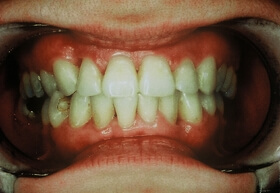

Több, mint tízéves koronák és az íny visszahúzódása a frontfogak ajak felőli oldalán

Felső négy frontfog korona cseréje és az íny visszahúzódásának korrekciója a szájpadból vett kötőszöveti lebennyel